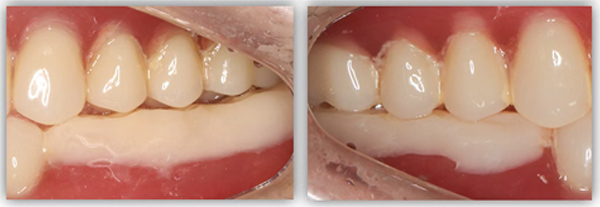

为满足患者的需求,我为她制订了一个即拔即种、种植后早期负重的方案,把五个治疗步骤缩减为三步。首次来院时,我为她完成了拔牙、种牙和安装基台,6周后来院拆线和取模,两周后完成牙冠修复,也就是戴牙。整个治疗周期仅8周,不到两个月就完成了。

6号牙也就是第一磨牙,是最早萌出的恒牙,比较容易龋坏。它虽然不在前牙美学区,不太容易影响容貌,但出于对美学的高要求,我在设计方案时也考虑了是按常规流程先拔牙,再备洞,还是以修复为导向,先按现有的牙冠来确定未来修复体的形状,再去反推种植体植入的位置。后者对医生来说难度更高一些,但更有利于复原天然牙的形态。

为保证这个方案的顺利实施,我通过查阅文献去印证方案的可行性,还为她建议了适合的种植体,原来三个月的骨结合时间能缩短为两个月,种植体功不可没。

这位患者不到60岁,但由于后牙全部缺失多年,残留的前牙已松动且上下无法接触,他基本没办法正常咀嚼,人非常消瘦。完成治疗后我跟踪了这个病例一年,从前后对比照片可以看出,能正常吃东西后他的脸上渐渐也有肉了。